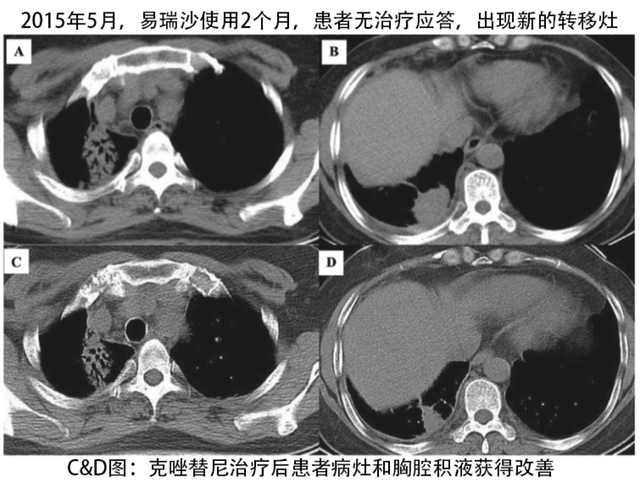

基于以上的分子诊断结果,患者开始使用易瑞沙治疗,计量为每天250mg,然而临床评估没有发现能有获益,2个月之后,发现胸膜出现转移病灶,大小为3.0厘米×3.0厘米,PET-CT揭示了胸膜、右肋和肝脏有多个转移灶。

2015年6月,患者开始使用克唑替尼治疗,每天两次,计量为250mg,患者主诉不适和疼痛症状迅速消失,6个月之后,CT扫描显示患者对克唑替尼治疗产生部分应答,直至2016年4月,患者仍然病情稳定,没有显示不适的症状。